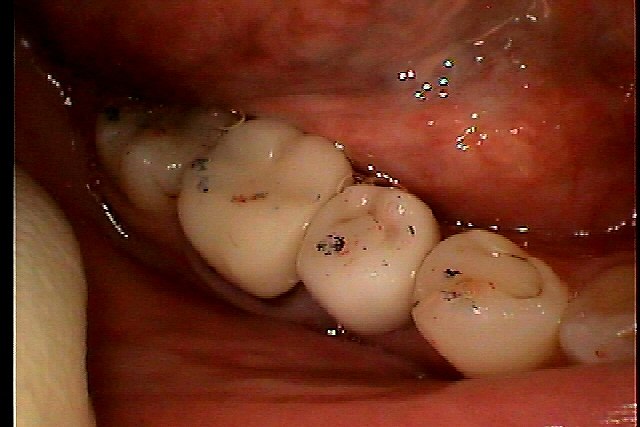

インプラント上部構造の作成 オールセラミックにて作成していきます|お知らせ |広島市安佐南区の歯科医院 インプラント上部構造の作成 オールセラミックにて作成していきます トップ お知らせ・ブログ お知らせ インプラント上部構造の作成 オールセラミックにて作成していきます インプラント上部構造の作成 オールセラミックにて作成していきます カスタムアバットメントの作成 アバットメント装着時 アバットメント装着時のデンタル 上部構造が入りました オールセラミックにて作成していきました 後ろの6番も治療していきます 根の治療をしています ファイバーコアを立ててオールセラミックにて作成していきました きれいに仕上がりました Web診療予約 初めての方へ 選ばれ続ける理由 院内設備について 歯が痛いしみる一般歯科 歯がぐらぐらする歯周病 健康な歯を保ちたい予防歯科 子供の虫歯予防をしたい小児歯科 銀歯をセラミックに審美歯科 白い歯を目指しませんか?ホワイトニング 矯正専門医がいるので安心矯正歯科 抜けた歯を補いたいインプラント・入れ歯 医院案内 スタッフ紹介 メリィハウス歯科クリニックオフィシャルホームページ ラベンダー歯科クリニックオフィシャルホームページ お知らせ・ブログ ホーム 診療科目 一般歯科 歯周病治療 予防治療 小児歯科 審美治療 ホワイトニング 矯正歯科 入れ歯・インプラント マウスピース矯正 初めての方へ 院長・スタッフ 設備紹介 医院案内・アクセス メニューを閉じる